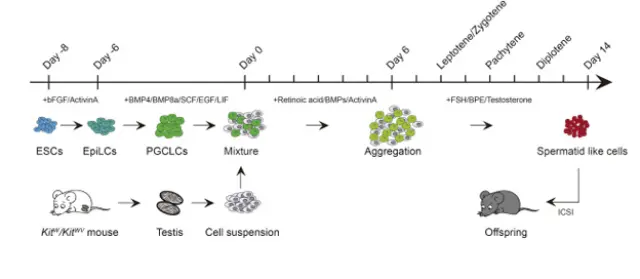

El primer paso de este procedimiento consistió en exponer a las células madre embrionarias de ratón a distintos compuestos químicos para convertirlas en células germinales primordiales. Después, los investigadores procedieron exponiéndolas a hormonas sexuales como la testosterona y a otras células testiculares. Como consecuencia, se cumplieron con las condiciones biológicas necesarias para que la meiosis tuviese lugar con normalidad.

Para poner a prueba el descubrimiento, siguiendo con el estándar de oro propuesto por sus colegas, el equipo de investigadores chinos inocularon estas células en óvulos de ratón. Para sorpresa de todos, los embriones se desarrollaron con normalidad y de ellos nació descendencia sana y fértil.